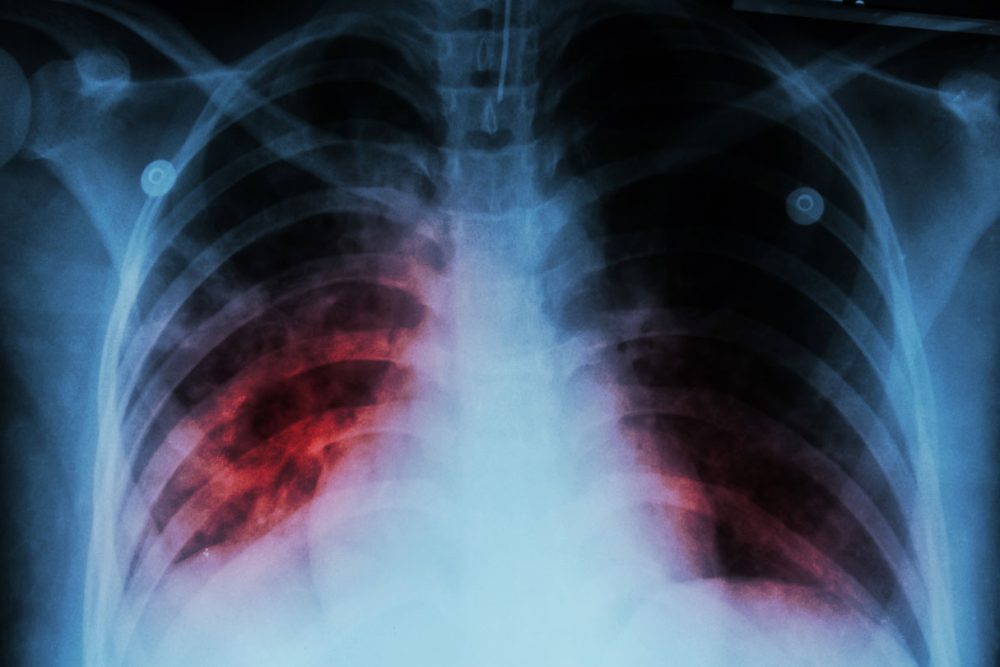

The Janssen Pharmaceutical Companies of Johnson & Johnson (Janssen), announced the submission of a Type II Variation application to the European Medicines Agency (EMA) for the Company’s medicine Sirturo (bedaquiline). A supplemental New Drug Application (sNDA) to the FDA was also submitted in August 2023. Sirturo is indicated in adults and pediatric patients (5 years to less than 18 years of age and weighing at least 15 kg) as part of combination therapy of pulmonary tuberculosis (TB) due to multi-drug resistant Mycobacterium tuberculosis. The approved indication may vary per country. These submissions reflect the Company’s longstanding commitment to patients affected by multidrug-resistant TB (MDR-TB), one of the world’s most significant global health challenges.

The applications include data from the Phase III STREAM Stage 2 study (NCT02409290), which is a Post-Marketing Requirement in the U.S., a Specific Obligation in the EU and a Post-Marketing Commitment in several other countries. STREAM Stage 2 is the first large-scale, randomized, multi-country clinical study to evaluate the efficacy and safety of an all-oral bedaquiline-containing regimen for MDR-TB. The study compared an all-oral, nine-month bedaquiline-containing regimen to the control regimen of a nine-month injectable-based regimen for the treatment of MDR-TB. The results were published in The Lancet in November 2022.